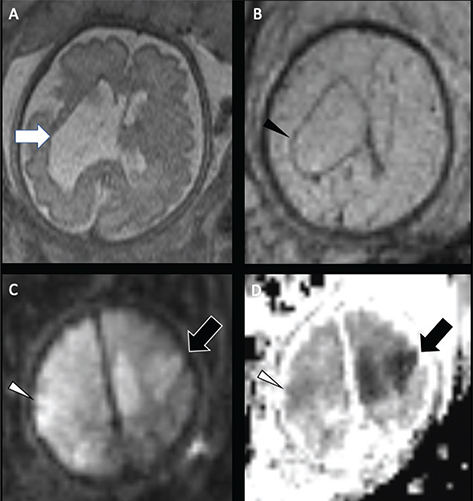

Periventricular venous infarction occurs in preterm infants as a consequence of germinal matrix hemorrhage, typically prior to 32 weeks of gestation (11). Germinal matrix hemorrhage may secondarily cause compression of the medullary veins, resulting in focal venous infarction in the periventricular white matter (100). Primary thrombosis of deep medullary vein can also be seen in full term neonates with congenital heart disease or with dehydration/metabolic acidosis, in the absence of germinal matrix hemorrhage, hypothesized to be related to hypoperfusion or impaired cerebral blood flow, and resulting in periventricular white matter venous infarct, often hemorrhagic (101103). The “iris sign,” a fan-shaped appearance of restricted diffusion or hemorrhage, most prominent in the deep frontal white matter, is a pathognomonic imaging sign of medullary vein thrombosis (Figure 10) (104). Delayed findings of periventricular venous infarction include periventricular white matter volume loss sparing the cortex and basal ganglia, focal irregularity of the ventricular margin, and hemosiderin staining (105). If spontaneous venous thrombosis is identified, the patient should be evaluated for disorders of coagulation (30, 97, 106113).

Fig 10

Figure 10. Medullary vein thrombosis and periventricular venous infarctions. Ex-premature at 32 weeks of gestation neonate, axial T2-weighted image (A) shows intraventricular hemorrhage (Black arrowhead), medullary veins thrombosis, and periventricular venous infarctions (arrows). A 7-day-old full-term neonate with severe dehydration. Sagittal T1-weighted (B) and axial GRE (C) images shows acute thrombus in the straight sinus (black arrow) and torcular and extensive thrombosis of the deep periventricular medullary veins (white arrowheads). Case courtesy of Dr. Tamara Feygin, Department of Radiology, Children’s Hospital of Philadelphia.